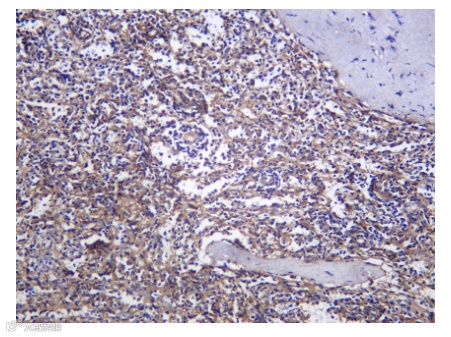

TAMs在肿瘤组织中的分布并非均一。M2样TAMs常富集于肿瘤侵袭前沿和低氧/基质区域,以促进局部浸润和血管生成;而M1样TAMs可能更多见于某些肿瘤的核心区域。这种空间异质性与患者预后密切相关。

图2 肿瘤相关巨噬细胞在肿瘤微环境中的分布和密度